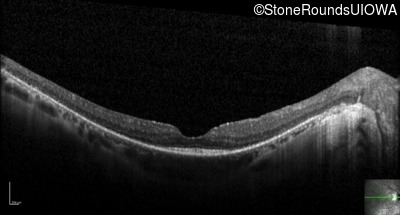

Optical Coherence Tomography - Right - 20/40 +1

Exemplar / OCT Stack

OCT Stack